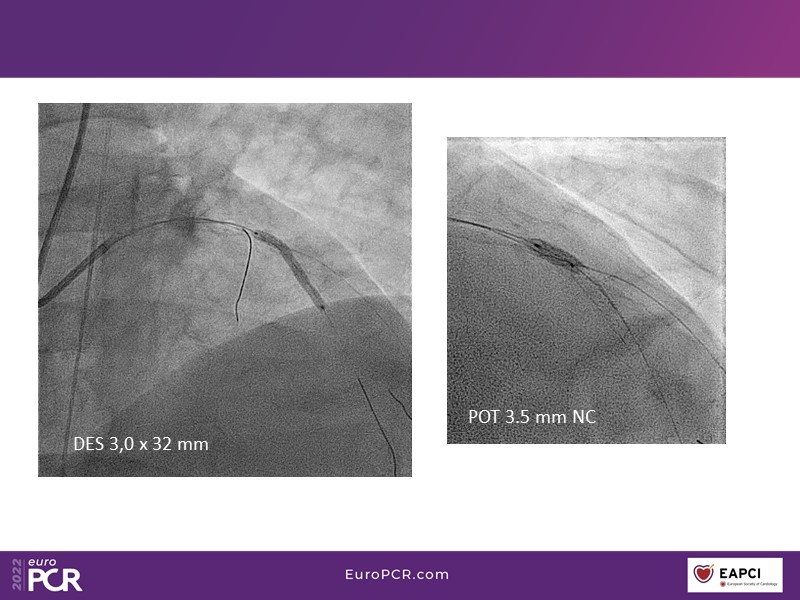

Conquer calcium with intravascular lithotripsy (IVL): cases and clinical data

This EuroPCR 2022 session mainly focuses on the DISRUPT CAD studies: hear discussion on the latest DISRUPT CAD clinical evidence supporting the use of IVL across different calcium morphologies, appraise the most recent one-year OCT-pooled analysis of the DISRUPT CAD III and IV studies, and learn about the differences in female PCI outcomes with IVL versus Rota.